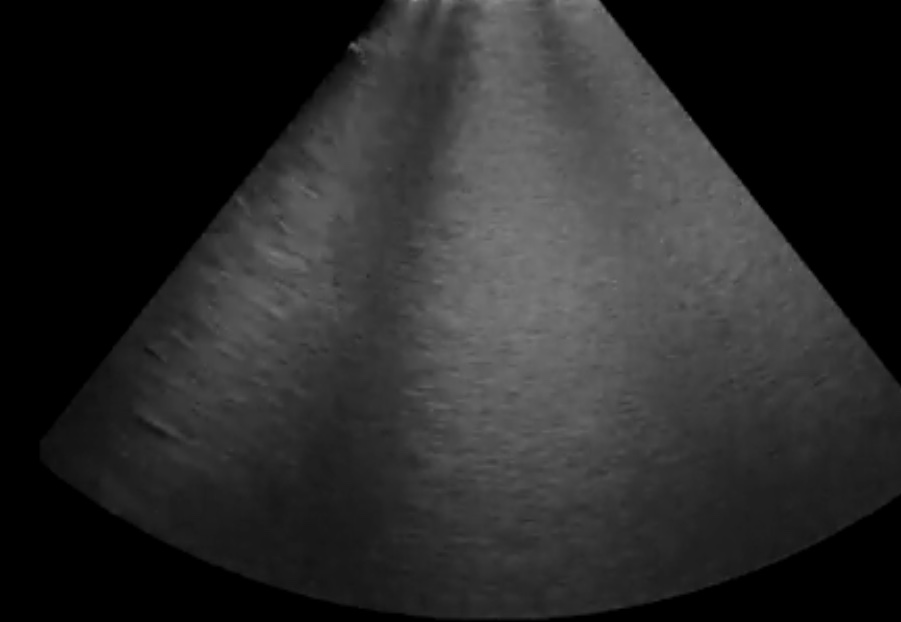

- Диагностика отека легких (кардиогенного, некардиогенного);

- Диагностика пневмоторакса;